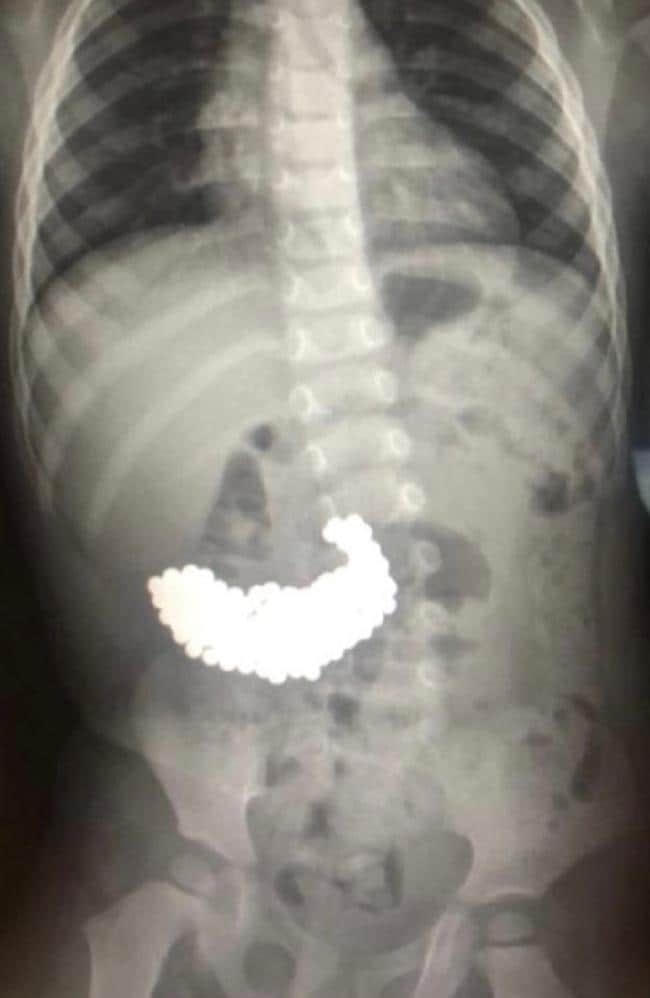

Tại bệnh viện, các bác sĩ vô cùng sốc khi phát hiện nhiều vật thể kim loại bên trong dạ dày bé. Hình ảnh phim chụp X-quang cho thấy có hàng trăm viên bi nam châm dính vào nhau trong dạ dày của cậu bé.

Các bác sĩ đã nhanh chóng tiến hành phẫu thuật nội soi và lấy ra tổng cộng 209 viên bi nam châm. Ca phẫu thuật kéo dài 2 giờ, các bác sĩ tiết lộ một số viên bi có gờ sắc nhọn, có thể đâm thủng niêm mạc dạ dày của bé trai. Sau ca phẫu thuật, sức khỏe của bệnh nhi tiến triển tốt.